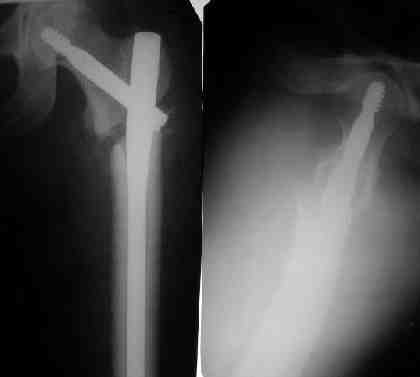

К сожалению под рукой только одна картинка от этой операции.

Я пошел на операцию имея стерильным и обычный бедренный гвоздь ChM и реконструктивный.

Когда открыто убрали DHS встали перед выбором, что ставить? Так, как это был подвертельный перелом - поперечная линия на уровне малого вертела то поставили обычный бедренный гвозь и один прокс блокирующий винт, который затянули компрессирующей заглушкой.